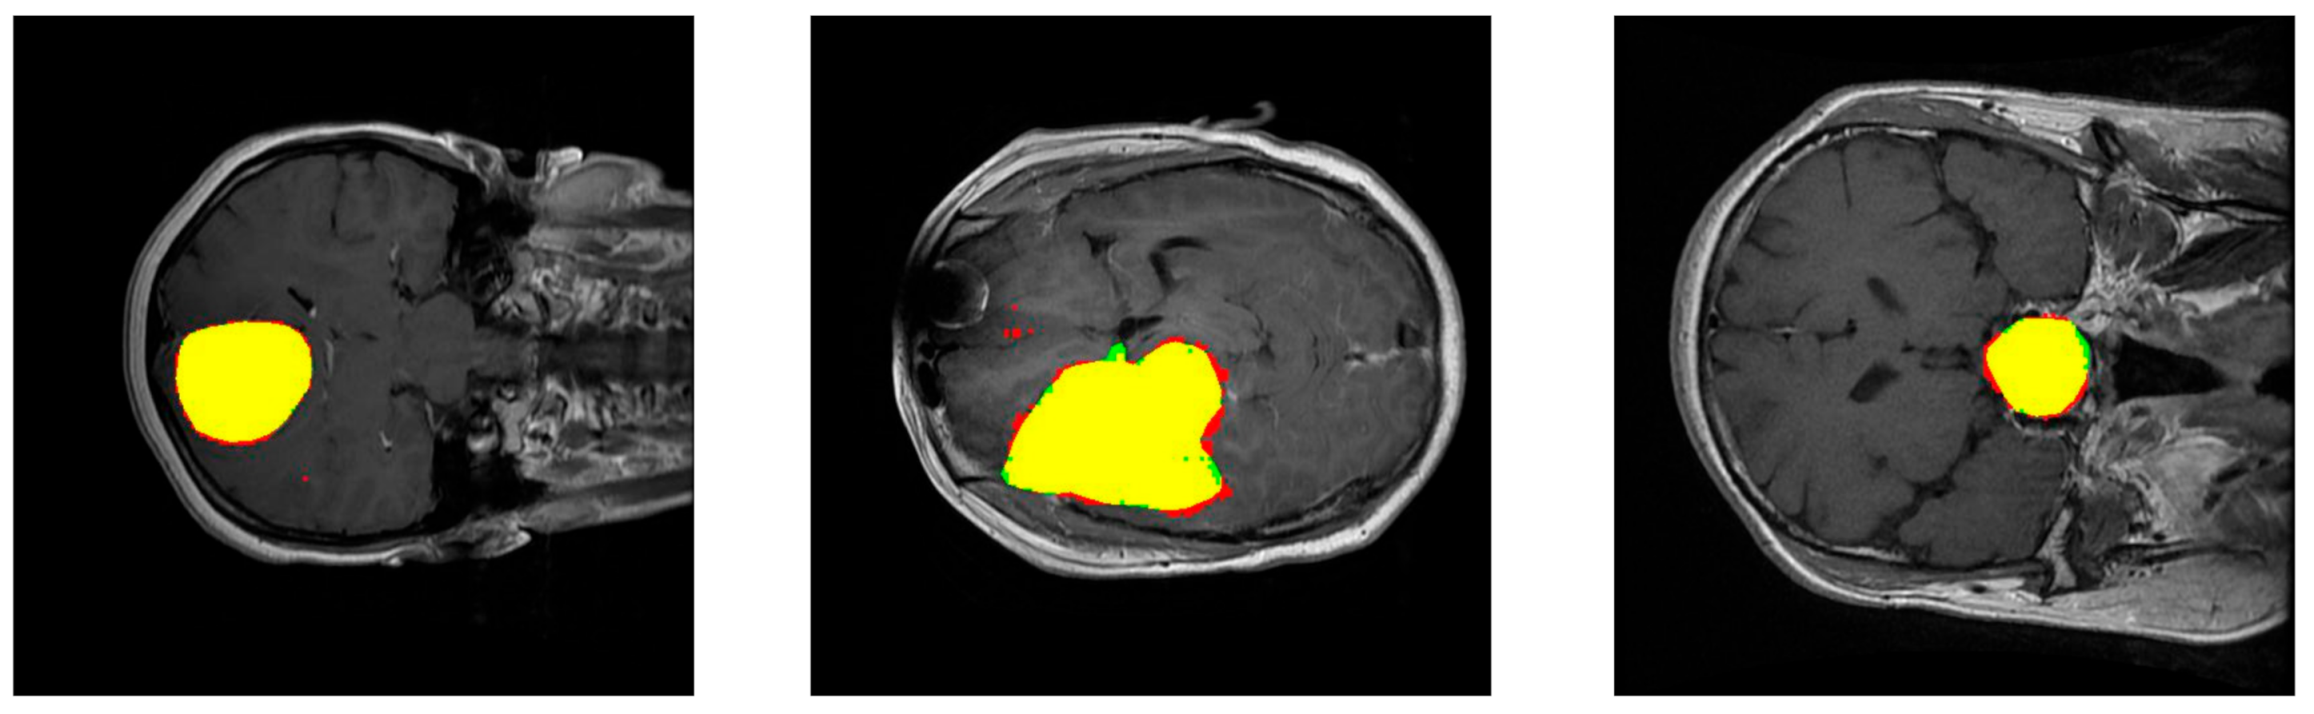

Figure 4 shows the performance of our method for three slices. Figure 4—left—corresponds to a slice with a meningioma tumor, Figure 4—center—shows a glioma tumor, and Figure 4—right—a pituitary tumor. The images show the tumor segmentation obtained, . To mark them with different colors, color images were generated where the predicted tumor region is filled with red color, the ground truth tumor region, , is colored green, and the intersection of those two regions appears in yellow.

Figure 4.

Examples of results of the proposed method for three slices corresponding to meningioma, glioma, and pituitary tumors, respectively. The images show the tumor segmentation: The region detected is shown in red while the ground truth region is shown in green. As a result, the intersection region is shown in yellow.

The segmentation metrics obtained are shown in Table 1. The Dice index, which is inversely related to the number of false positives and false negatives extracted (see Equation (3)), is the largest for images with meningioma, then with pituitary tumor, and the lowest with glioma. Therefore, the proportion of false positives and false negatives is the lowest in the prediction of meningiomas and is the largest in the prediction of gliomas. The Sensitivity index, which computes the ratio between true positives and the ground truth (see Equation (4)), led to the same ranking (the largest value for images with meningioma, then with pituitary tumor, and the lowest value with glioma), although the value of this index is closer for images with meningioma and pituitary tumor. The prediction of gliomas had the lowest relation of true positives with respect to the ground truth. On the contrary, the pttas index is the largest for images with glioma, then with pituitary tumor, and the lowest with meningioma. The values of this index, which measures the relation in size between the correctly labeled tumor regions and all the predicted tumor regions in the images, indicates that for gliomas our model misclassified a lower proportion of pixels as belonging to the two other brain tumors than for meningiomas or pituitary tumors. It can be observed that the different features of the three analyzed brain tumors and the terms including in the segmentation metrics led to a different ranking in the segmentation of the three tumors. The values obtained for all the segmentation metrics are remarkable with average values of Dice = 0.828, Sensitivity = 0.940, and pttas = 0.967.

Regarding the pttas index histogram (see Figure 5—right), we can see a very outstanding behavior. Around value 0, there are just a few samples. In these samples the predicted tumor is wrong as pttas is lower than 1/3 (pttas measures the ratio to the right label). If pttas is larger than 1/3, it means that the tumor type prediction was correct. The rest of the samples are found in values above 0.4, which means that they have all been correctly predicted. The high values of the Sensitivity index (see Figure 5—center) are due to the fact that almost all the tumor regions have been correctly extracted in the processed images (regions in yellow in Figure 4). A greater amplitude in the Dice histogram (see Figure 5—left) reflects the existence of false positives and false negatives. However, the Dice index results are relatively high, so the number of false positives and false negatives is quite low.